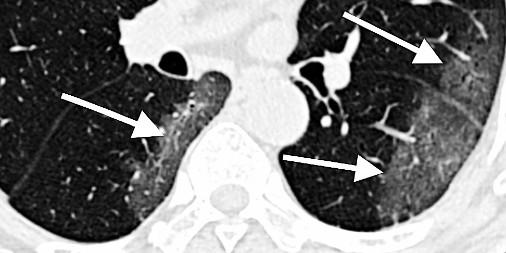

The features of infected lungs and hearts seen on medical images can help assess disease severity, predict response to treatment, and improve patient outcomes. However, a major challenge is to rapidly and accurately identify these signatures and evaluate this information in combination with many other clinical symptoms and tests. The MIDRC goals are to lead the development and implementation of new diagnostics, including machine learning algorithms, that will allow rapid and accurate assessment of disease status and help physicians optimize patient treatment.

"This effort will gather a large repository of COVID-19 chest images," explained Guoying Liu, PhD, the NIBIB scientific program lead on this effort, "allowing researchers to evaluate both lung and cardiac tissue data, ask critical research questions, and develop predictive COVID-19 imaging signatures that can be delivered to healthcare providers."